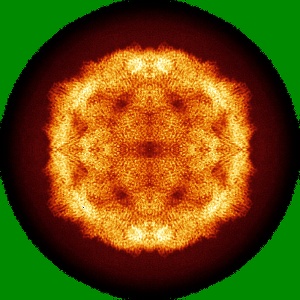

Cryo-EM structure of Coxsackievirus B1 empty particle

Single-particle3.4 Å